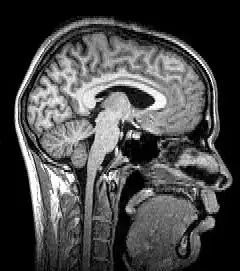

Neuroimagem ou imagem cerebral é o uso de várias técnicas para imagem, direta ou indiretamente, da estrutura, função/farmacologia do sistema nervoso. Essa é uma disciplina relativamente nova dentro da medicina, neurociência e psicologia.[1] Os médicos que se especializam no desempenho e na interpretação da neuroimagem no cenário clínico são denominados neuroradiologistas.

A ressonância magnética (MRI) usa campos magnéticos e ondas de rádio para produzir imagens de duas ou três dimensões de estruturas cerebrais de alta qualidade sem uso de radiação ionizante (raios-X) ou traçadores radioativos.